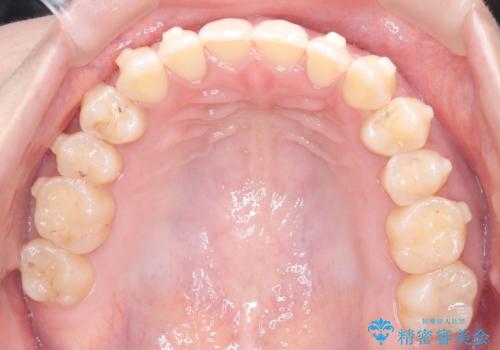

再矯正 前歯のガタツキをマウスピース矯正で治療したい

- 前に矯正治療をしたが、後戻りしてガタツキが出てきたので、治したいとのことで来院されました。

ワイヤー治療とマウスピース矯正、2通りの治療を提案させていただき、マウスピース矯正治療を希望されましたので、インビザラインによる治療を開始しました。

前歯のガタツキを改善する治療法として、マウスピース矯正が適していることが多いです。

マウスピース矯正は、金属製のブラケットやワイヤーを使用せずに、透明なマウスピースを装着して歯を移動させる方法です。そのため、目立たず、痛みも少ないです。